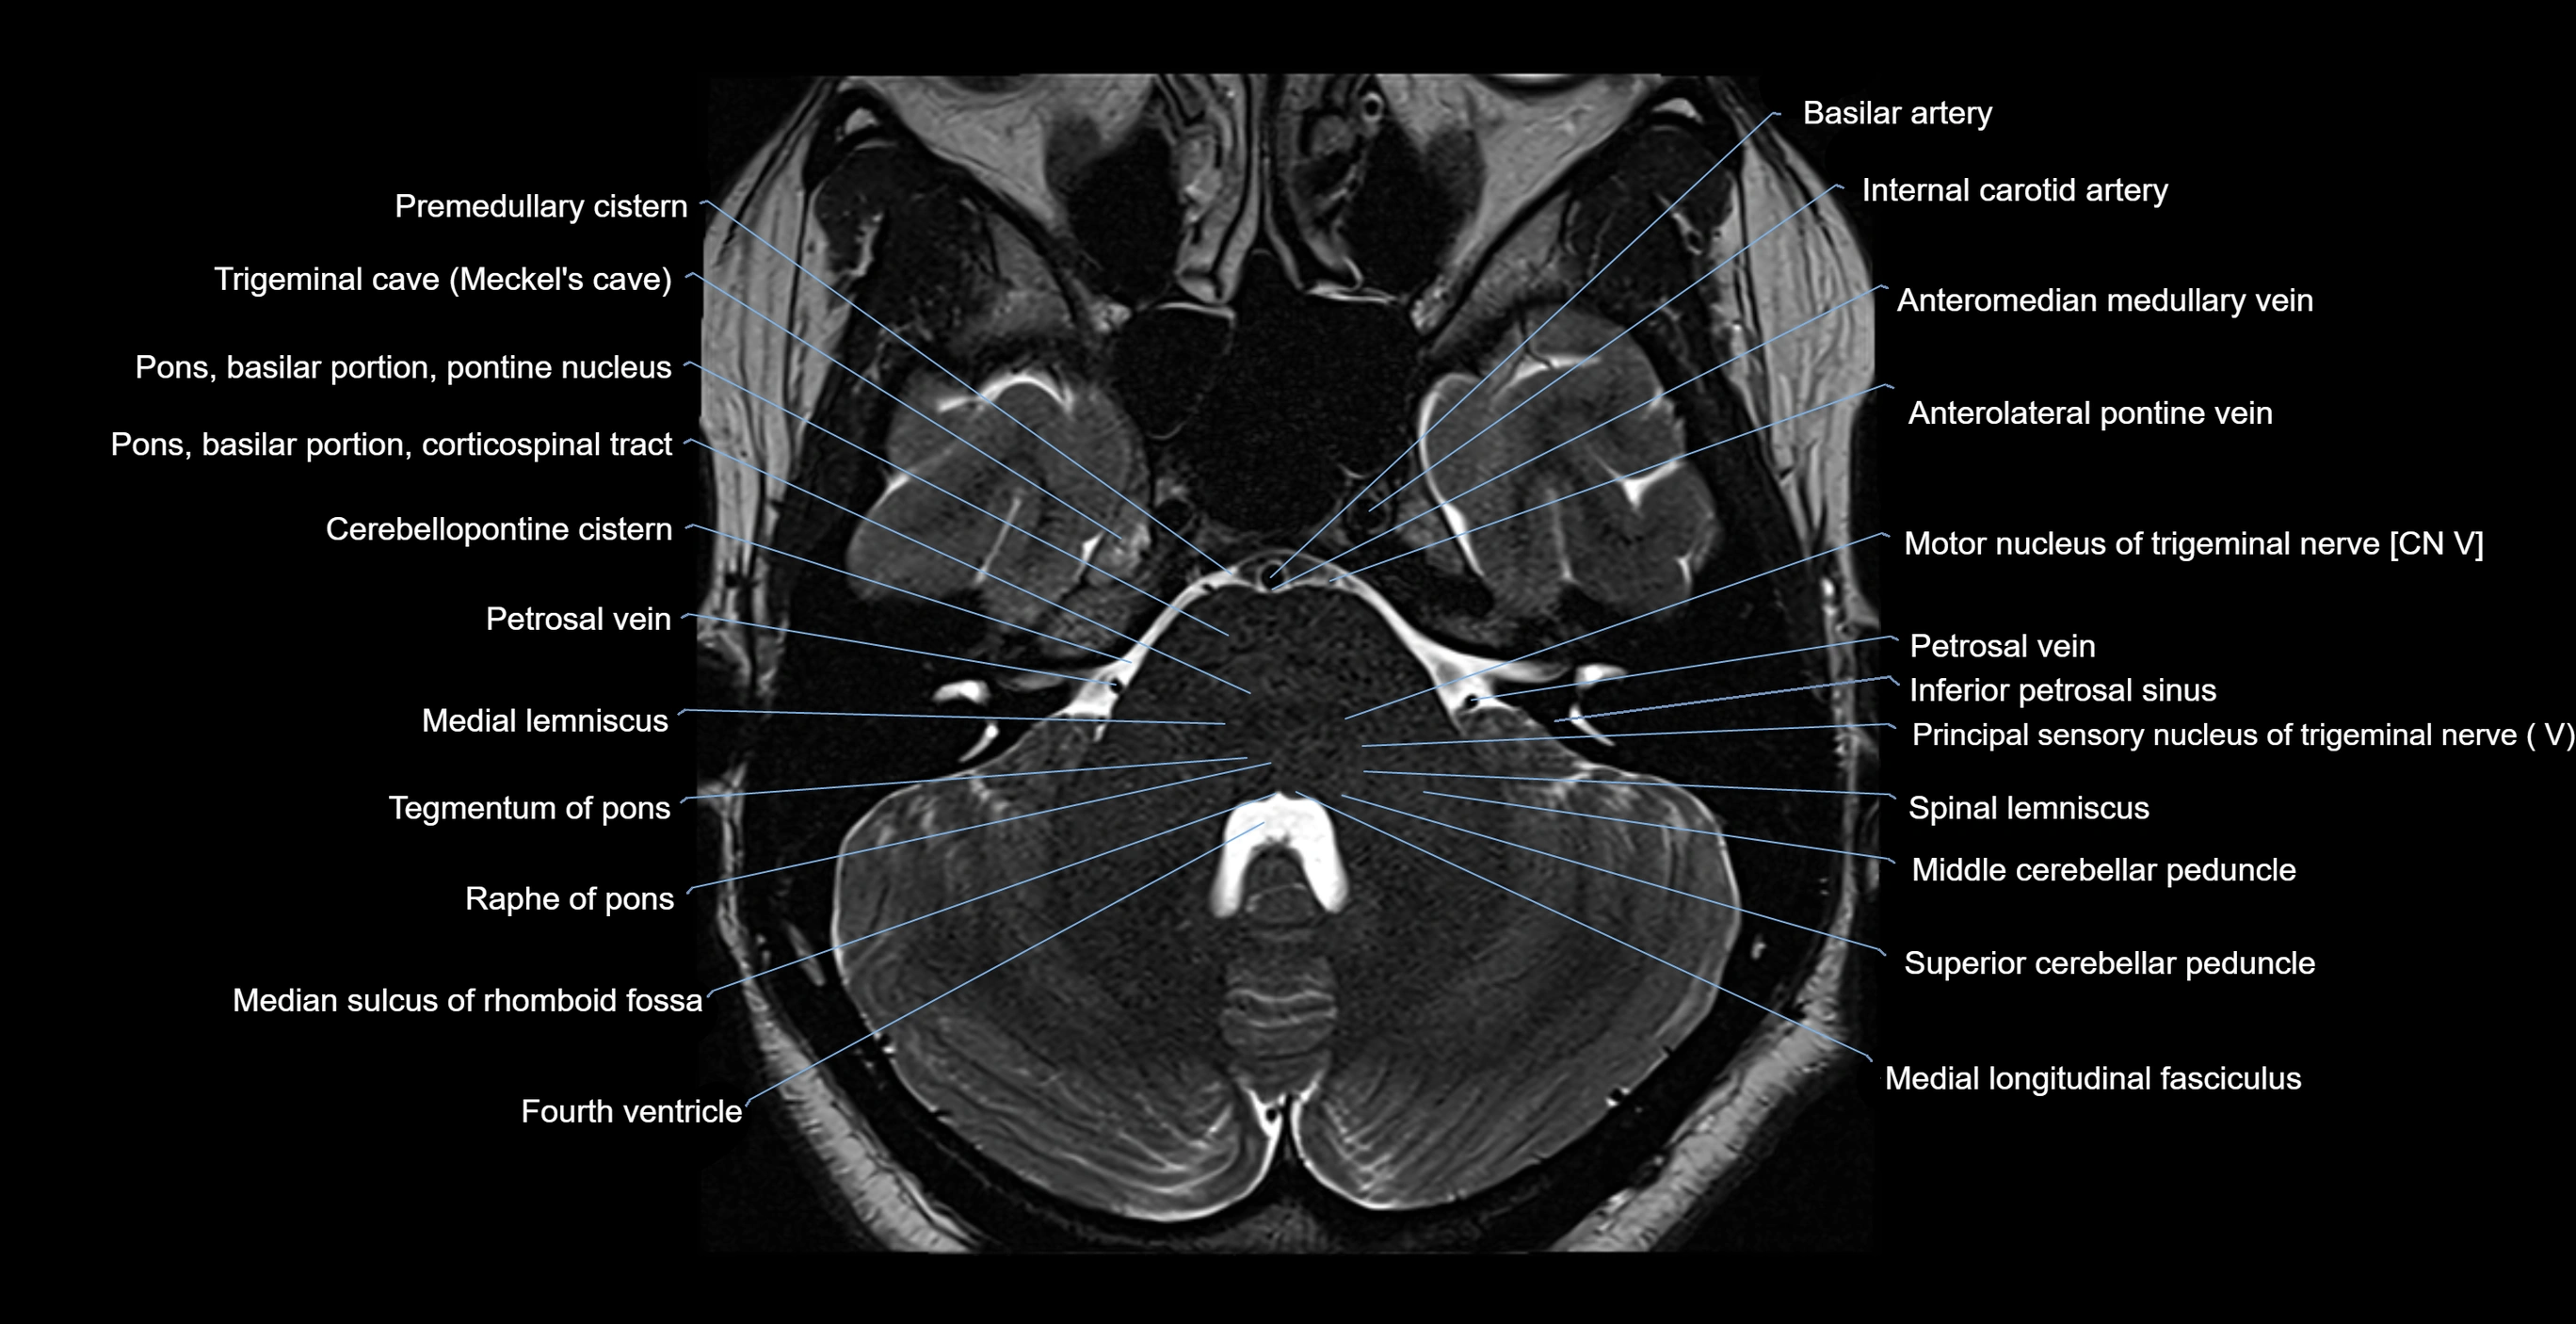

MRI images